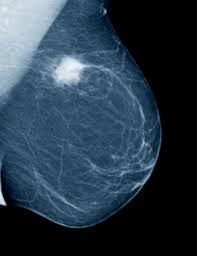

Any area that does not look like normal tissue is a possible cause for concern. Magnetic resonance imaging (mri) of the breast — or breast mri — is a test used to detect breast cancer and other abnormalities in the breast. Breast cancer and some noncancerous (benign) breast conditions can appear white on a mammogram. Microcalcifications, which look like white specks on a mammogram. What does an abnormal mammogram look like? Breast mri images are combined, using a computer, to create detailed pictures. Mammograms may show suspicious areas of the breast, white spots, and microcalcifications. In addition to mammograms, ultrasound and mri may also be used to take a closer look at changes in the breast. Tumors are likely to be smaller when doctors detect them early, which can. This type of cancer also changes the appearance of your breasts. A lump or tumor will show up as a focused white area on a mammogram. This appears most commonly as streaking, known as linear enhancement. There are few risks associated with mammography.

Breast Cancer Ge News from www.ge.com Healthy mammograms can still vary in appearance. The dye collection in the breast can also look clumpy or appear in a section of the breast, depending on the involvement of dcis. It can also be used to investigate the cause of breast problems, such as a breast mass, pain and nipple. Cancers may be seen as masses (like a ball, but usually with an irregular shape), areas of asymmetry that resemble normal tissue, calcifications (white specks), and/or areas of architectural distortion (imagine the puckering caused by pulling a thread in a piece of fabric). There are few risks associated with mammography. If you've had a mammogram before, the radiologist should compare your old mammogram to the new one to look for changes. After a mammogram that didn't show anything, and a sonogram that found the lump, i was diagnosed with stage 2 breast cancer. The doctor reading your mammogram will be looking for different types of breast changes, such as small white spots called calcifications, larger abnormal areas called masses, and other suspicious areas that could be signs of cancer.

Microcalcifications, which look like white specks on a mammogram. They will look carefully at the mammogram to interpret the results. Tumor size is an important factor in breast cancer staging, and it can affect a person's treatment options and outlook. Breast mri images are combined, using a computer, to create detailed pictures. Breast cancer can appear as a spiculated mass, cluster of tiny calcifications, smoothly marginated mass, area of subtle distortion or be invisible on. Magnetic resonance imaging (mri) of the breast — or breast mri — is a test used to detect breast cancer and other abnormalities in the breast. Calcifications are calcium deposits within the breast tissue and they look like small white spots. A breast cancer tumor on a mammogram is often irregular with edges that don't look smooth. A 3d mammogram is used to look for breast cancer in people who have no signs or symptoms. A rash isn't the only visual symptom of inflammatory breast cancer. A mammogram can show breast changes such as calcifications, masses, or other symptoms that might be cancer. This appears most commonly as streaking, known as linear enhancement. What does cancer look like on a mammogram?

This appears most commonly as streaking, known as linear enhancement. As with all abnormalities seen on breast imaging, the diagnosis of dcis requires a sample of tissue or biopsy. What does breast cancer look like on a mammogram? Calcifications are calcium deposits within the breast tissue and they look like small white spots. Breast cancer can appear as a spiculated mass, cluster of tiny calcifications, smoothly marginated mass, area of subtle distortion or be invisible on.

Mammogram Images Normal And Abnormal from www.verywellhealth.com Any area that does not look like normal tissue is a possible cause for concern. The appearance of normal breast tissue on a mammogram varies from person to person, and no two mammograms look the same. A woman's breast tissue also changes over time, and it is not uncommon for benign lumps, cysts or calcifications to form with age. What does cancer look like on a mammogram? Tumors may be benign or cancerous. Abnormalities such as cancerous tumors usually appear brighter because they are denser. Cancers may be seen as masses (like a ball, but usually with an irregular shape), areas of asymmetry that resemble normal tissue, calcifications (white specks), and/or areas of architectural distortion (imagine the puckering caused by pulling a thread in a piece of fabric). Calcifications are calcium deposits within the breast tissue and they look like small white spots.

Cancers may be seen as masses (like a ball, but usually with an irregular shape), areas of asymmetry that resemble normal tissue, calcifications (white specks), and/or areas of architectural distortion (imagine the puckering caused by pulling a thread in a piece of fabric).

Any area that does not look like normal tissue is a possible cause for concern. Invasive breast cancer can appear as a white patch or mass on a mammogram. You may notice dimpling or pitting, and the skin on your breast. A rash isn't the only visual symptom of inflammatory breast cancer. The milk ducts carry your breast milk from lobules, where milk is produced, to your nipple. Magnetic resonance imaging (mri) of the breast — or breast mri — is a test used to detect breast cancer and other abnormalities in the breast. A lump or tumor will show up as a focused white area on a mammogram. 1 the gray areas correspond to normal fatty tissue, while the white areas are normal breast tissue with ducts and lobes. A spiculated breast mass, which has spikes extending out from the main mass, is often highly suggestive of cancer. Macrocalcifications, which look like small white dots on a mammogram. It's so important to listen to the messages our bodies are telling. In addition to mammograms, ultrasound and mri may also be used to take a closer look at changes in the breast. Breast cancer can appear as a spiculated mass, cluster of tiny calcifications, smoothly marginated mass, area of subtle distortion or be invisible on.